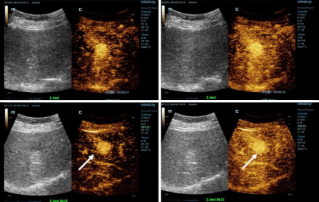

![more-precise-diagnoses-with-hifr-ceus.thumb.319.319 HiFR CEUS? ?? ?? ??? ??]() HiFR CEUS? ?? ?? ??? ??CEUS(?? ?? ???)? ?? ???? ???? ?? ? ? ?? ?? ???? ?? ??? ?? ???????. ??? ?? ? ??? ?? ????? ?? 10? ? ?? ??? ??? ??? ? ?? HiFR CEUS(????? ?? ?? ???)???.??? | ?? ?? 2022-12-16

HiFR CEUS? ?? ?? ??? ??CEUS(?? ?? ???)? ?? ???? ???? ?? ? ? ?? ?? ???? ?? ??? ?? ???????. ??? ?? ? ??? ?? ????? ?? 10? ? ?? ??? ??? ??? ? ?? HiFR CEUS(????? ?? ?? ???)???.??? | ?? ?? 2022-12-16 -